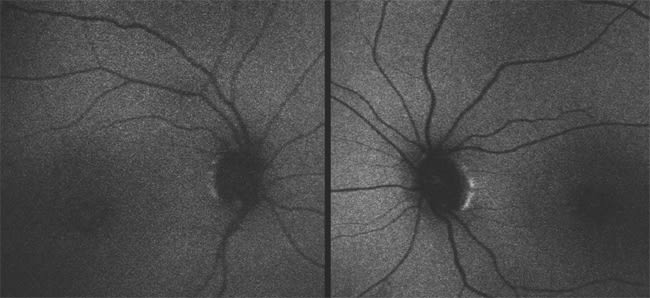

Patient 3 has high hyperopia (+8.00 OU), nystagmus, VA of only LP and a normal-appearing fundus. She was diagnosed at the age of six months because of poor responses to visual stimuli, photophobia and undetectable responses on ERG testing. Fundus photos at 25 years of age are shown in Figure 6, and autofluorescence images are shown in Figure 7.

Figure 6. Fundus photographs of a 25-year-old patient with mutations in GUCY2D show normal optic discs, mild attenuation of the arterioles and normal maculas. There is some minor RPE mottling in the far periphery.

Figure 7. Autofluorescence images of the same patient as in Figure 6 demonstrate normal autofluorescence, as is typically seen in patients with GUCY2D mutations.

Patient 3 has LCA due to mutations in the GUCY2D (guanylate cyclase) gene. GUCY2D is one of the key enzymes within the phototransduction cascade. Mutations in this gene prohibit reopening of cyclic guanosine mono-phosphate (cGMP)–gated cation channels after photoexcitation, thereby maintaining a state resembling continuous light exposure. Patients with mutations in this gene typically have VA in the LP range, with a few reports of VA up to 20/40.9 In most cases, the fundus remains normal throughout life, although granular pigmentary changes may sometimes develop in the periphery.

Recent studies have shown that macular SD-OCTs in most patients with LCA due to mutations in GUCY2D are relatively normal.9 Adeno-associated vector-based gene replacement therapy studies in knockout mouse models show promise as a future therapeutic intervention.10 Because the VA is typically in the range of LP from birth and appears static, there is a limited time frame during which gene therapy may be administered in these patients in order to retain some visual function.